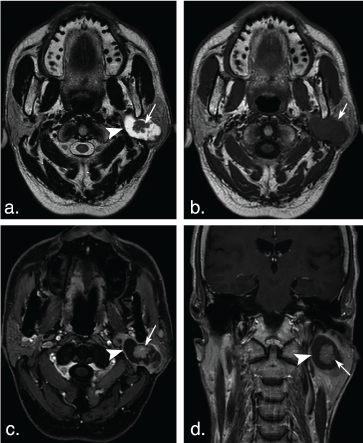

Figure 7: Different shape of the cystic areas in the parotid gland tumors. (a) T2 weighted image shows a large ovoid cystic hyperintense cystic area (arrow) in a basal cell adenoma of a 57-year-old man. (b) T2 weighted image shows several ovoid cystic hyperintense cystic areas (arrows) in Warthin tumors of a 52-year-old man. (c) T2 weighted image shows a small round cystic hyperintense cystic area (arrow) in the heterogeneous pleomorphic adenoma of a 39-year-old female with on. (d) T2 weighted image shows a small ovoid cystic hyperintense cystic area (arrow) in a Warthin tumor of an 84-year-old man. View Figure 7

Three of 9 BCAs (33.33%), 34 of 62 PAs (54.84%) and 29 of 58 WTs (50%) were solid-looking tumors. Three of 9 BCAs (33.33%), 4 of 62 PAs (6.45%) and 3 of 58 WTs (5.17%) had an irregular nonenhanced cystic area within the tumor. Three of 9 BCAs (33.33%), 24 of 62 PAs (38.71%) and 26 of 58 WTs (44.83%) had an ovoid nonenhanced cystic area within the tumors (Figure 7). There was no significant difference between BCA and PA (P = 0.052), and between BCA and WT (P = 0.056).